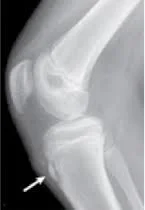

Em alguns casos, no entanto, pode haver fragmentação e destacamento da TAT, que podem ficar abaixo ou dentro do tendão patelar. Durante a pratica esportiva ou até mesmo em atividades do dia a dia, estes fragmentos instáveis se chocam com a tíbia, causando reação inflamatória cônica com queixas de dor e atrofia muscular, limitando a performance esportiva.

Assim como a maior parte dos autores, acredito que, nestes casos, está indicada a remoção cirúrgica do fragmento. Segundo a literatura, havendo uma boa reabilitação pos-operatoria focada no fortalecimento e reequilíbrio muscular, em 85 a 90% dos casos, houve retorno pleno a atividades esportivas pré-lesionais.